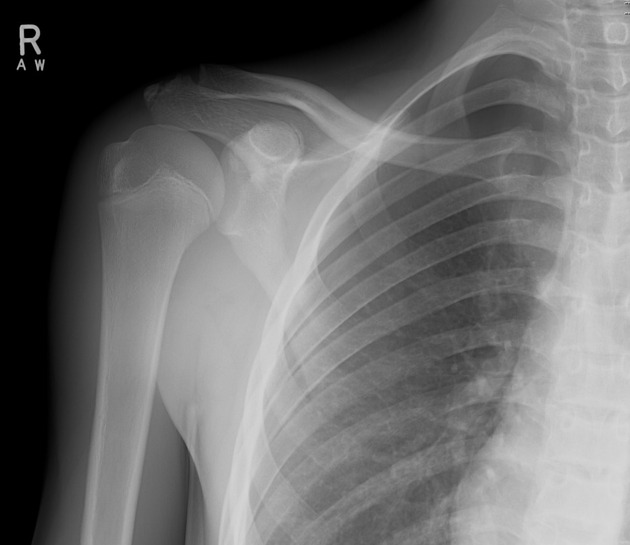

Describe the abnormality demonstrated.

Bony fragment on the inferior surface of the (right) glenoid, consistent with a bony Bankart lesion. Increased opacity on the supero-lateral surface of the (right) humeral head may indicate a Hills-Sachs deformity.